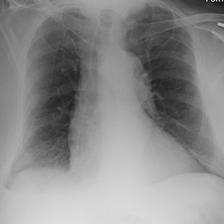

In Figure A.3, we show examples of self-attention rollout [1] maps for pleural effusion and consolidation, including radiologist-annotated bounding boxes surrounding the corresponding pathology in each prior and current image.

To model the attention flow through the transformer encoder block, we first average each attention weight matrix across all heads, subsequently we multiply the matrices between every two layers. For every block we add the identity matrix in order to model the residual connections. Last, we only keep the top 10 of attention weights per block to reduce noise in the final rollout map. In contrast to [21], we do not visualize the rollout map with respect to a [CLS] token. Instead, we choose a reference image patch from the center of the radiologist-annotated bounding boxes, marked with in Figure A.3.

We find that the rollout maps in Figure A.3 are in good agreement with radiologist-annotated bounding boxes, i.e., the reference patch attends to other patches within the bounding boxes in the prior and current image. In addition, we find that BioViL-T is robust to pose variations, e.g., in Figure A.3 (a) we show that despite the vertical shift between prior and current image, the reference patch attends to the correct image patches in the prior image.

To further assess the robustness of BioViL-T against pose variations between prior and current images, we performed multiple rotations to the prior image within a pair and computed rollout maps from the same reference patch in the current image. Figure A.5 shows that BioViL-T consistently attends to the corresponding anatomical region independently of the spatial transformation applied, demonstrating that registration is not needed.